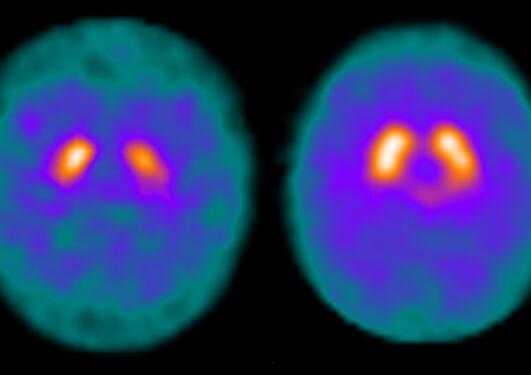

"First of all, the target organ of these diseases, the brain, is not directly available to us for research. In other disease, such as cancer, we are often able to obtain a sample of the affected tissue and analyze it – even test to which drugs it responds best – but we cannot do the same thing with the brain of a living patient. We are limited to either studying the brain indirectly, through imaging such as MRI, or obtaining tissue after death, at autopsy", he says.

Together with his team, they are well underway in this effort. Tzoulis' work has greatly advanced the knowledge of how mitochondria, the cells' power-generators, are involved in Parkinson's disease, and provided evidence that they may, indeed, hold the key to therapy. Inspired by these findings, Tzoulis started clinical trials of compounds promoting mitochondrial function. The research group has just completed an early (phase I) trial showing that the treatment is safe, reaches the brain and influences its metabolism. Encouraged by these findings, they are now conducting the NO-PARK trial, a large (phase II) trial with 400 patients, aiming to determine whether this therapy can delay the progression of Parkinson’s disease. (Information regarding these trials can be found on clinicaltrials.org: NCT03816020, NCT03568968).